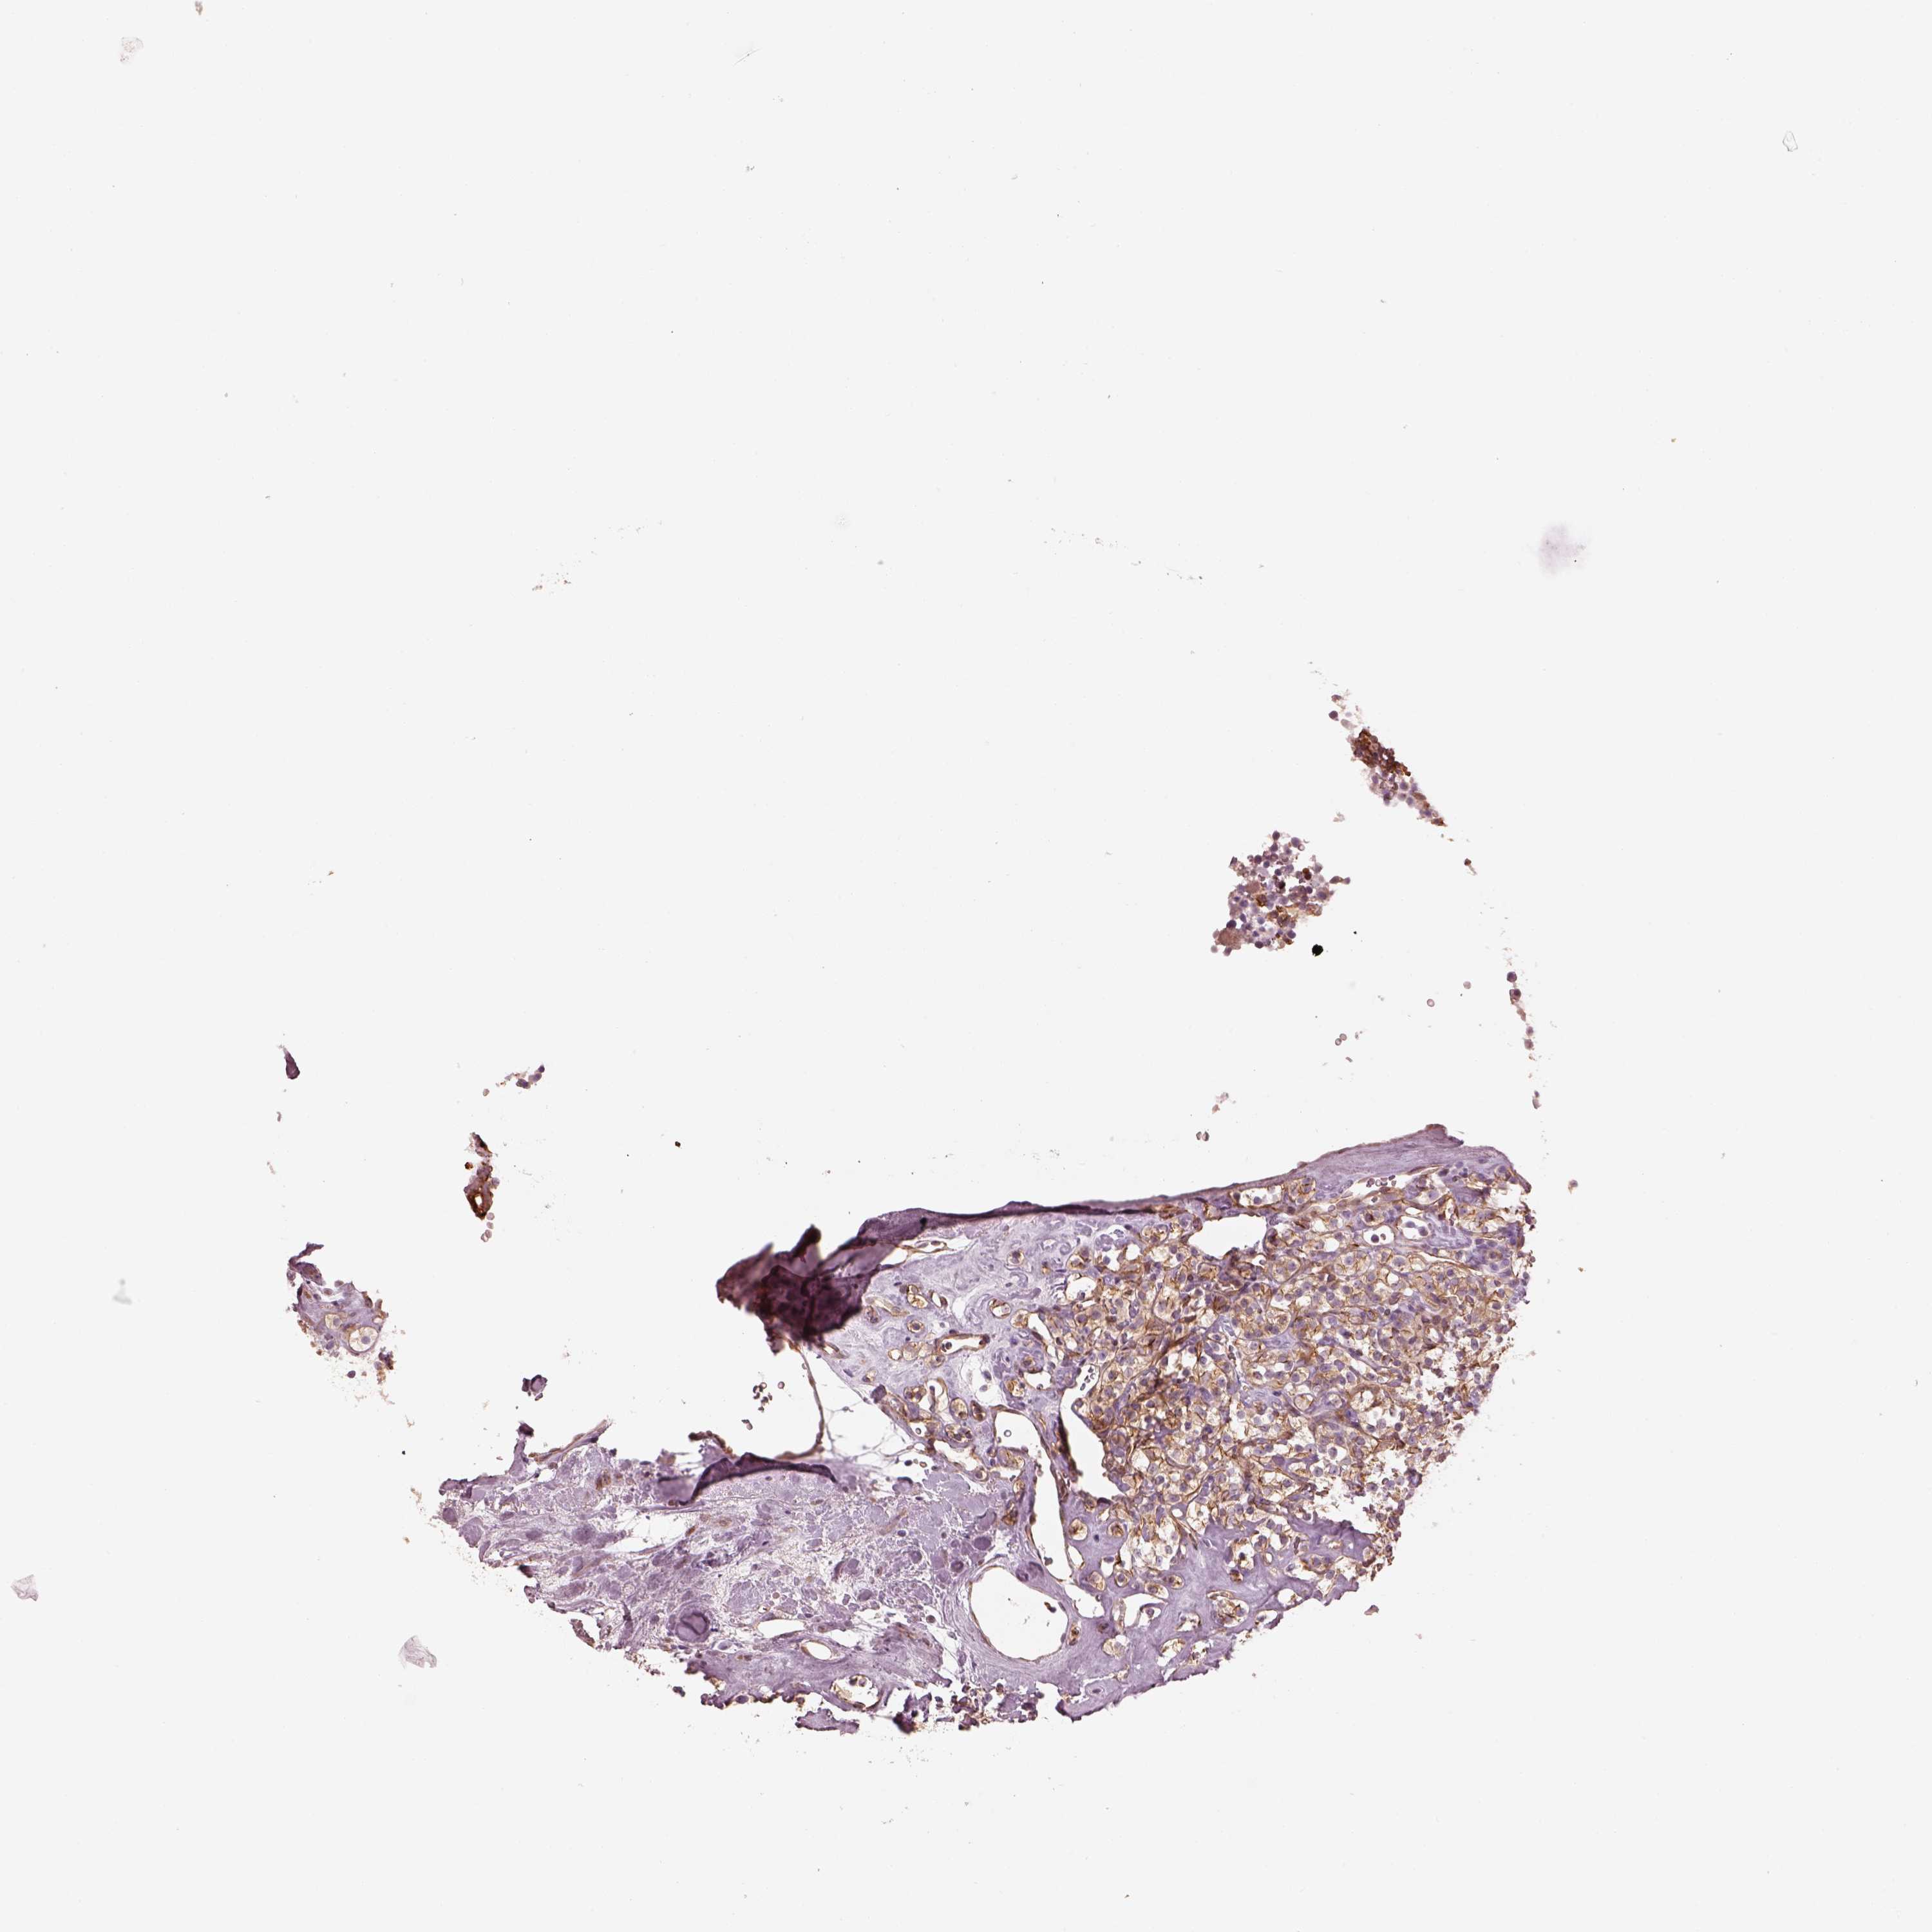

KIDNEY RENAL CLEAR CELL CARCINOMA (VALIDATION) - Interactive survival scatter ploti

The Survival Scatter plot shows the clinical status (i.e. dead or alive) for all individuals in the patient cohort, based on the same data that underlies the corresponding Kaplan-Meier plots. Patients that are alive at last time for follow-up are shown in blue and patients who have died during the study are shown in red.

The x-axis shows the expression levels (FPKM) of the investigated gene in the tumor tissue at the time of diagnosis. The y-axis shows the follow-up time after diagnosis (years). Both axes are complimented with kernel density curves demonstrating the data density over the axes. The top density plot shows the expression levels (FPKM) distribution among dead (red) and alive patients (blue). The right density plot shows the data density of the survived years of dead patients with high and low expression levels respectively, stratified using the cutoff indicated by the vertical dashed line through the Survival Scatter plot. This cutoff is automatically defined based on the FPKM cutoff that minimizes the p-score. The cutoff can be changed by dragging the vertical line or by entering a cutoff value in the square labeled "Current cut-off".

Under the Survival Scatter plot the p-score landscape (black curve; left axis) is shown together with dead median separation (red curve; right axis). Dead median separation is the difference in median mRNA expression between patients who have died with high and low expression, respectively. It is calculated as follows: median FPKM expression of dead patients with high expression - median FPKM expression of dead patients with low expression. This is intended to aid the user in visually exploring custom cutoffs and the associated p-scores and dead median separation.

Individual patient data is displayed and can be filtered by clicking on one or more of the category buttons on the top of the page. Categories describing expression level and patient information include: high, low, alive, dead, female, male and tumor stages. The scale of the x-axis can be toggled between linear and log-scale by clicking on the "x log" button. Mouse-over function shows TCGA ID, patient information and mRNA expression (FPKM) for each patient.

& Survival analysisi

Kaplan-Meier plots summarize results from analysis of correlation between mRNA expression level and patient survival. Patients were divided based on level of expression into one of the two groups "low" (under cut off) or "high" (over cut off). X-axis shows time for survival (years) and y-axis shows the probability of survival, where 1.0 corresponds to 100 percent.

CRYM is not prognostic in Kidney Renal Clear Cell Carcinoma (validation)

: 6.76

Average pTPM 21.1

Number of samples 100